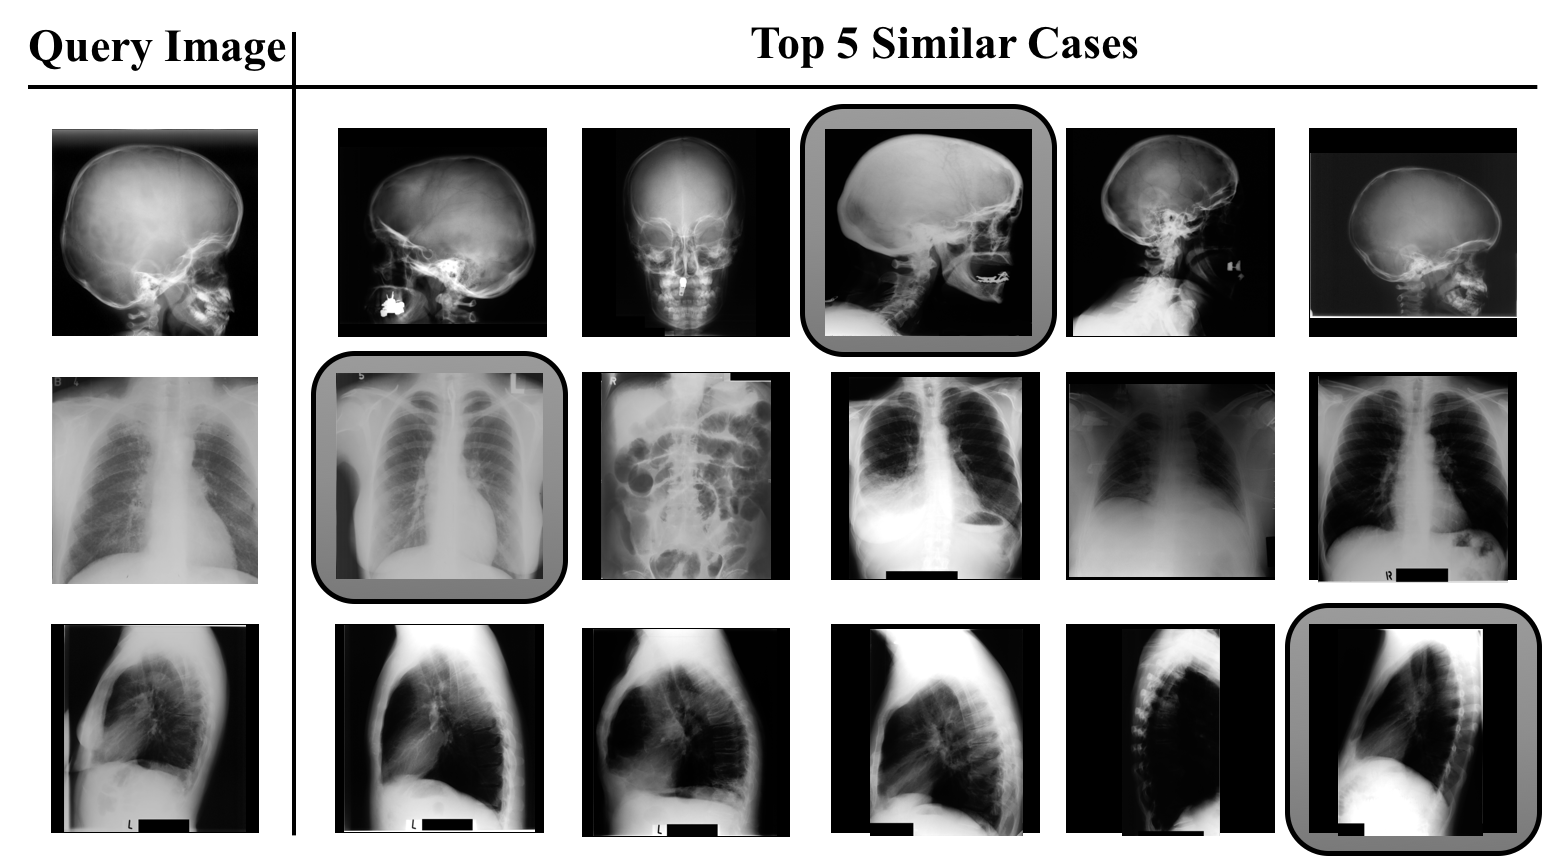

Investigating the applicability of the autoencoders in medical image retrieval, the lowest IRMA error of 313313313 was achieved by training a classifier using 161616 equidistant normalized Radon projections from pre-processed training images with a 10-fold cross validation and early stopping. Radon projections performed better than both the HOG features and raw pixel values. In addition, Radon projections were observed to consume less memory and to be faster (\approx 25GB of RAM for 2.5 hours) when compared to HOG (\approx 30GB of RAM for 3 hours) and raw images (\approx 35GB of RAM for 4.5 hours). Additionally, weighting the retrieval distances using the MLP classification probability is observed to consistently yield better results compared to simply using Euclidian distances. Fig. 3 shows the effect of weighting of similarity using classification probabilities. The images from left to right are sorted in increasing order of Radon projection similarity, wherein the highlighted image shows the best match after probability weighting.

Refer to caption

Figure 3: Examples for the “best match” (highlighted) using Radon projections. Each retrieved image has its own IRMA code which can be compared with the query’s IRMA code to calculate the retrieval error.